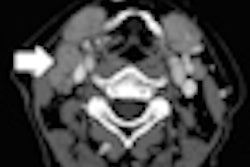

Oropharyngeal carcinoma patients treated with intensity-modulated proton therapy (IMPT) were half as likely to need feeding tubes compared to patients treated with intensity-modulated radiation therapy (IMRT).

The study from the MD Anderson Proton Therapy Center, presented on September 25 at the American Society for Radiation Oncology (ASTRO) annual meeting in Atlanta, also found that toxicity levels in oropharyngeal carcinoma patients treated with IMPT were much lower than in patients treated with IMRT.

Based on the results, lead researcher Dr. Steven J. Frank, associate professor of radiation oncology at MD Anderson, and colleagues stated that proton therapy may offer quality-of-life benefits for patients with tumors occurring at the back of the throat.

The researchers evaluated 25 oropharyngeal carcinoma patients treated with IMPT and 25 treated with IMRT. Five patients (20%) treated with IMPT required the use of feeding tubes, compared with 12 patients (48%) treated with IMRT.

IMPT patients were also spared from other serious side effects caused by the toxicity of IMRT, such as vomiting, nausea, hearing problems, and inflammation and ulceration of the digestive track. In addition, patients could better sustain their nutrition and hydration levels, often leading to faster recovery during and after treatment.

Based on the findings, MD Anderson has initiated a randomized phase II/III trial of IMPT versus IMRT for the treatment of oropharyngeal cancer. The institution plans to enroll 360 patients in the trial over the next five years.